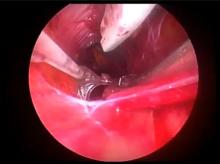

Joseph Zacharias of the Lancashire Cardiac Centre, Blackpool, United Kingdom, demonstrates an endoscopic vein harvesting technique, and reviews the evidence for and against endoscopic vein harvesting.

This presentation was originally given during the SCTS Ionescu University program at the 2015 Annual Meeting of the Society for Cardiothoracic Surgery in Great Britain and Ireland. This content is published with the permission of SCTS [3]. Please click here [4] for more information on SCTS educational programs.